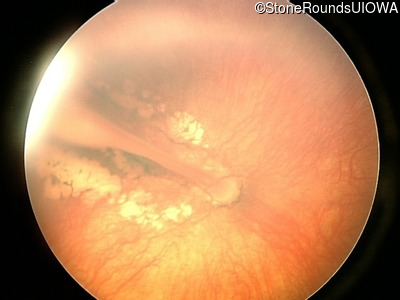

Fundus Photography - Right - 10/200

Exemplar